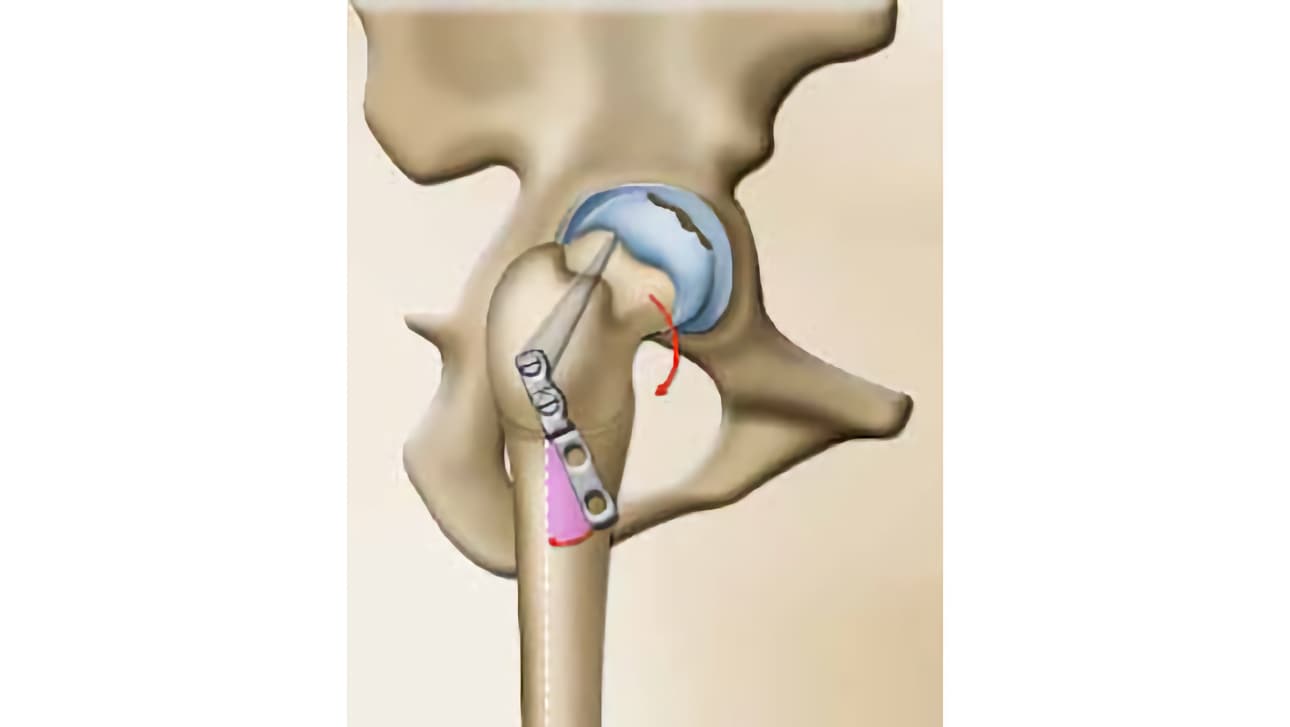

Υπάρχουν πολλές τεχνικές για να επιτευχθεί αυτό. Ο χειρουργός σας προτείνει εκείνη που θεωρεί κατάλληλη για την περίπτωσή σας. Έχετε βέβαια πάντα υπόψη σας ότι η χειρουργική έχει τα όριά της!